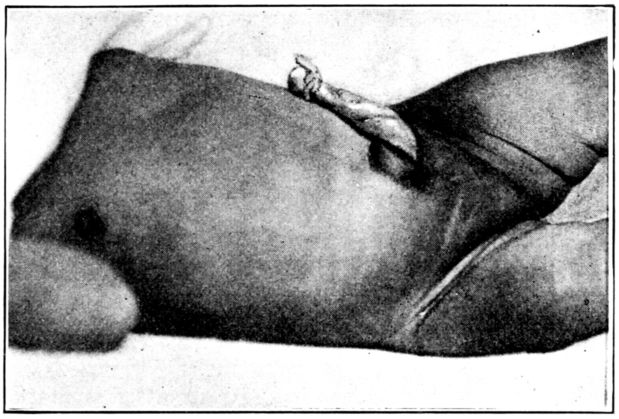

| 149. | Umbilical cord immediately after birth | 457 |

| 150. | The same four days later | 457 |

| 151. | Umbilicus immediately after separation of cord | 458 |

| 152. | Well healed umbilicus | 458 |